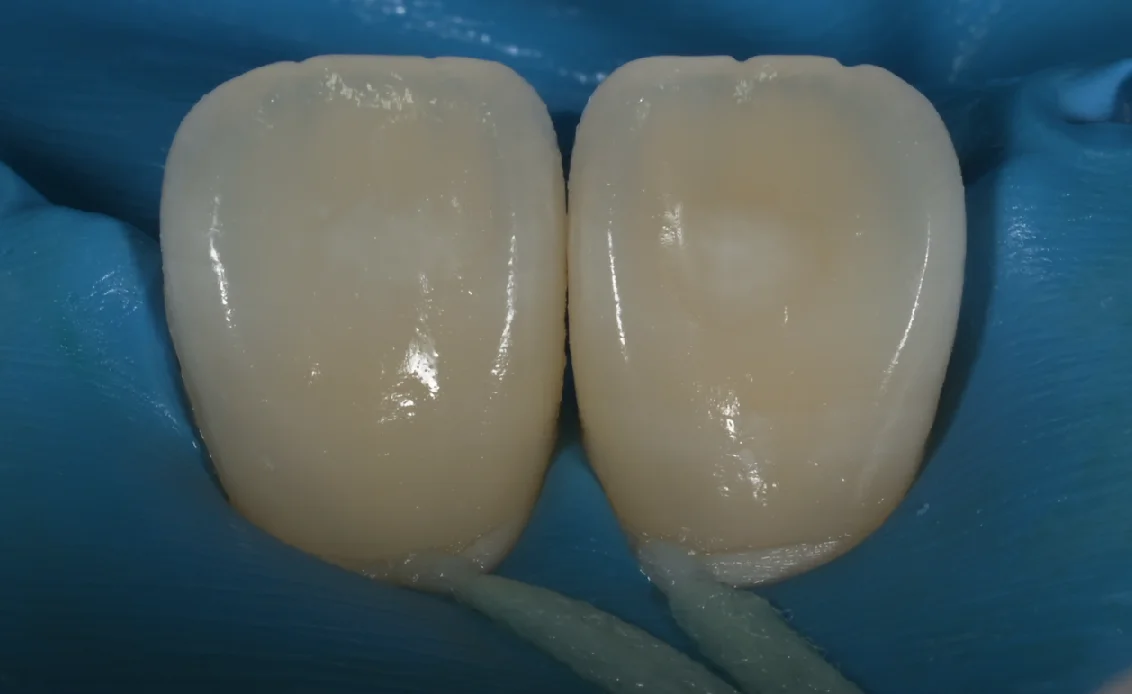

術後写真がこちらになります。

塩酸で歯の表層のエナメル質を一層溶かしながらそれをブラシで擦りつつ、エナメル質内部に存在している空気の層への通り道を作って・・・その通り道を通して、内部にレジンを流し込むのがこのICONという治療です。

研磨ブラシを使用して擦るので、歯の削る量は0.01〜0.05mmほどの本当に微々たるものですが、それでもゼロではないのでその点はご注意ください。

さて、ラバーダムを外したのがこちらになります。

随分と目立たなく、違和感が少なくなったのが分かるかと思います。

ゴムのマスクを強く歯茎に押し込むので一部出血していますが、出血自体は5分くらいで治って違和感も1〜2日で消えますので、そこはご安心ください。